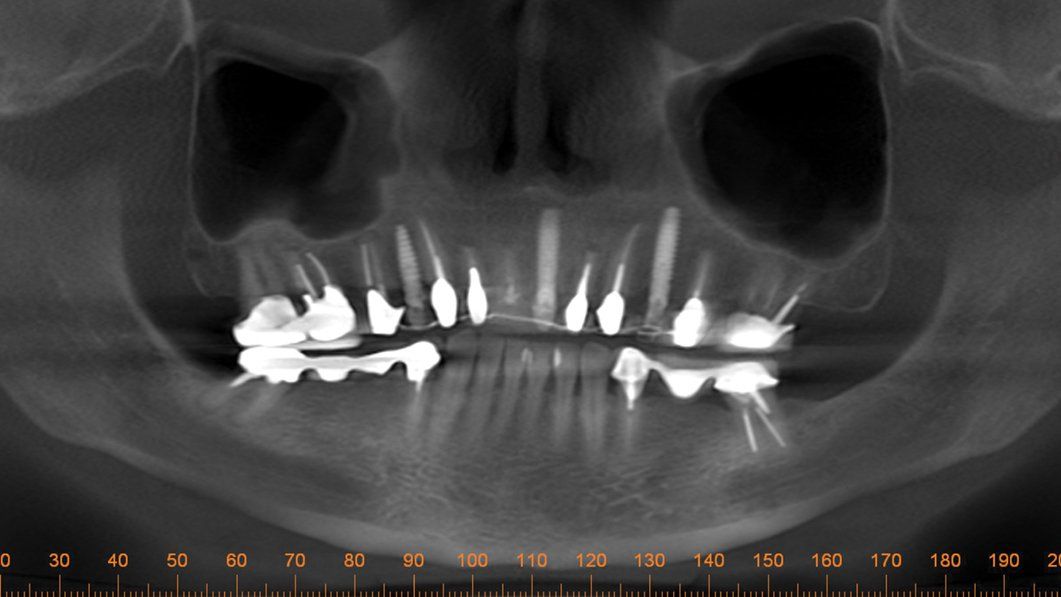

One day a 50 year-old patient and dentist friend of mine, (who already has multiple dental implants) came to my office and presented with a non-restorable fractured tooth number 8 (Figure 1). As you can see from the photograph, this looked to be a complicated extraction. As always, my treatment plan consists of proper imaging. With dental implant cases it usually involves the i-CAT. (Figure 2)